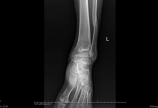

左踝关节骨折畸形愈合

患者男性,50岁,因左踝关节外伤后畸形7年伴行走疼痛入院。7年前因被树干致伤左踝关节,当地乡村医生保守治疗好转后左踝畸形行走疼痛。